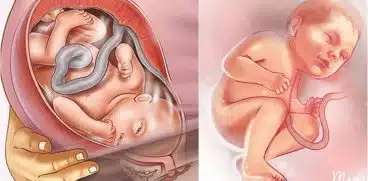

- Naștere naturală

- Naștere prin cezariană

- Nașterea prematură